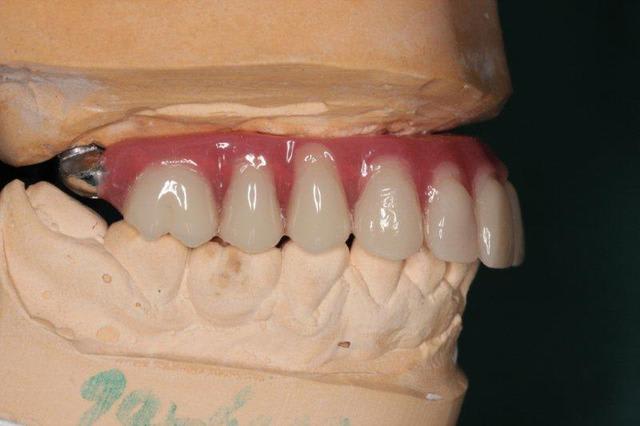

P'tite question, les vis qui tiennent la prothèse en place, sont des vis " plates", simple rainure.

L'axe de certains implants semble un peu trop palatin, mais bon, il n'y a pas de nonos...

1. C est toi qui es malhabile... Rien de plus simple : tu mets ttes tes vis ds la puits, tu les recouvres d homéoplasmine pour les empêcher de tomber hors des puits, tu poses en bouche et tu passes ton tournevis ds homéoplasmine pour visser Très simple et très efficace :-))))

2. Effectivemeznt les plaques zygomatiques ont des émergences palatines mais au définitif j ai ôté les piliers prlongateurs de 3.5 mm et du coup même si sortie palatine plus aucun "débordement" du puits de vissage en dehors de l arcade...

3.Ca fait 18 mois que les implants sont en charge donc tu as déjà une idée mais de manière générale ça fonctionne aussi bien qu pilotis à la mandibule... Un petit coup de waterpik léger et qques bains de bouches suffisent à entretenir tout ça correctement

Regarde le provisoire de la MCI : les émergences des plaques au niveau molaires font des bombés hors arcades suite à la pose de piliers monobloc de hauteur 3.5 mm

On pose ces piliers car il faut pouvoir retrouver facilement les têtes d implants 72 h plus tard pour poser la prothèse de transition